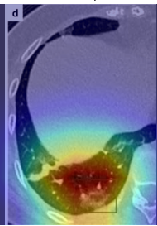

In a similar way, we consider classifying the test CT scans from the COVID-19 dataset by the DenseNet169 model and highlight the important regions considered for predictions. We present the original CT images and their localization maps in Figure 13. We can also see that our model is capable to detect the COVID-19 related regions as marked (small square in some images) by expert radiologists.

Figure 16 shows various CT scans where only one lung is visible. The CT scans are also extracted from the paper [58] and show different CT manifestations of COVID-19 pneumonia marked by red squares. The InceptionV3 model is capable to classify them correctly as COVID-19, although it is trained on CT scans where the entire lung is visible. Intriguingly, when applying Grad-CAM we can see that all regions of abnormalities are accurately localized. This also proves the potential of our model to detect COVID-19 abnormalities in CT images outside the dataset used for training.